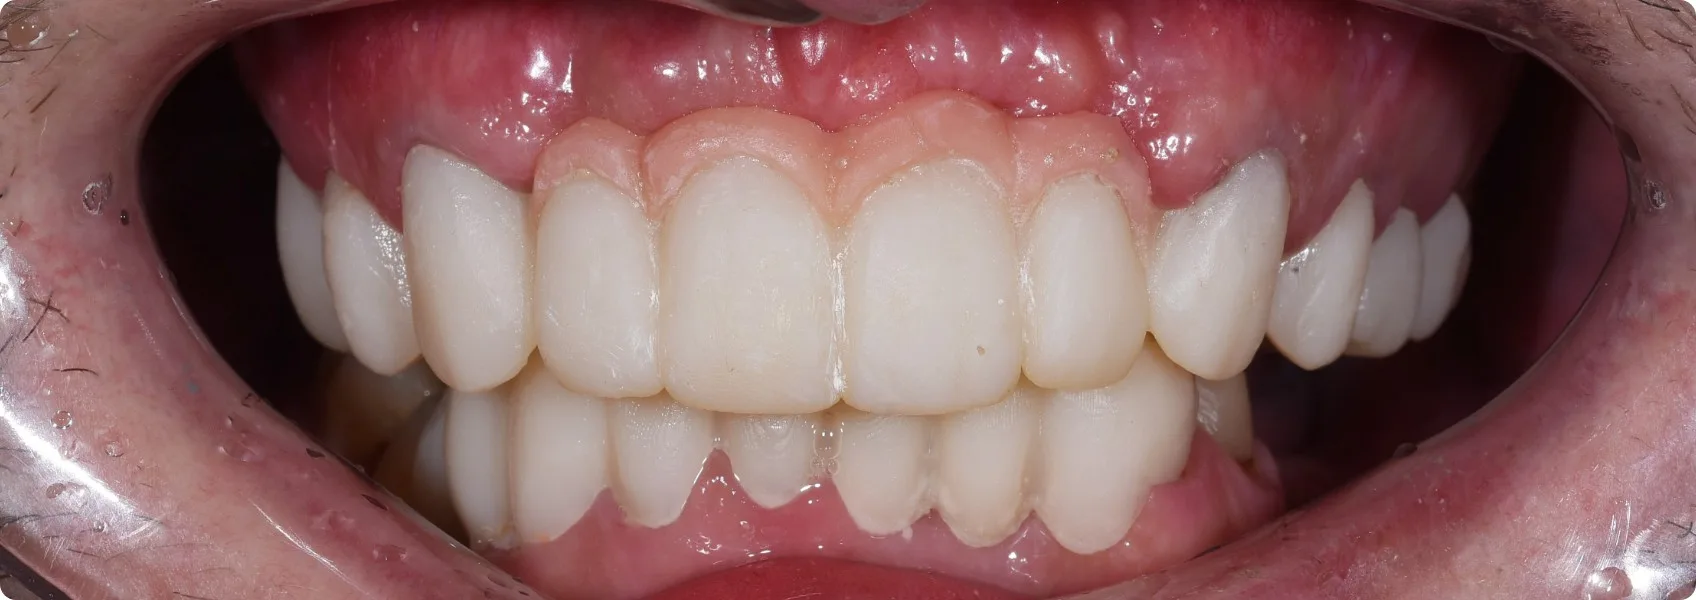

Patrząc na nowy uśmiech Pacjenta, trudno uwierzyć, jak daleką drogę przeszedł. Trudno też uwierzyć, że to nie jego własne, naturalne zęby.

Po wielu miesiącach precyzyjnej pracy, nadszedł ten wyczekiwany moment — oddaliśmy finalny górny most. Mimo że na dolnych zębach Pacjent nosi jeszcze prowizorium, efekt jest absolutnie zachwycający!

Ta odbudowa to dla nas prawdziwe dzieło sztuki. Idealnie odtworzona struktura zębów, sposób, w jaki naturalnie odbijają światło, naturalnie wyglądające dziąsło — każdy najdrobniejszy niuans jest dopracowany tak, by wiernie oddać piękno naturalnego, zdrowego szkliwa.

Dla tego Pacjenta to prawdziwa życiowa rewolucja. Nowe, pełne zęby to nie tylko odzyskanie pięknego uśmiechu i pewności siebie, ale przede wszystkim powrót do normalności — swobodnego jedzenia, wyraźnego mówienia i życia bez ciągłego bólu.